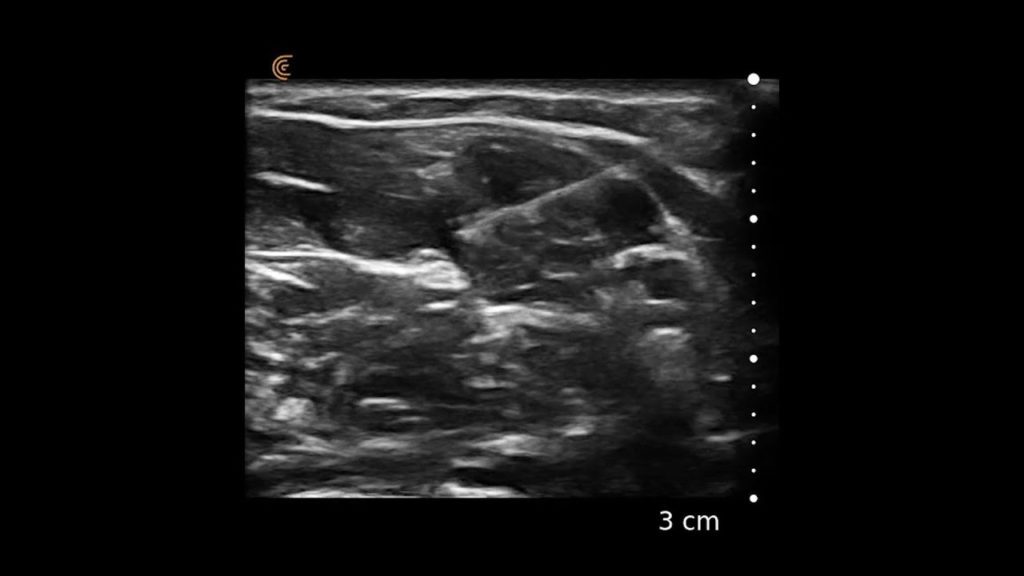

Using the jejunum as an important landmark, the hypoechoic jejunal lymph nodes can be identified. In this video Dr. Edwards explains the ultrasound appearance of normal jejunal nodes.